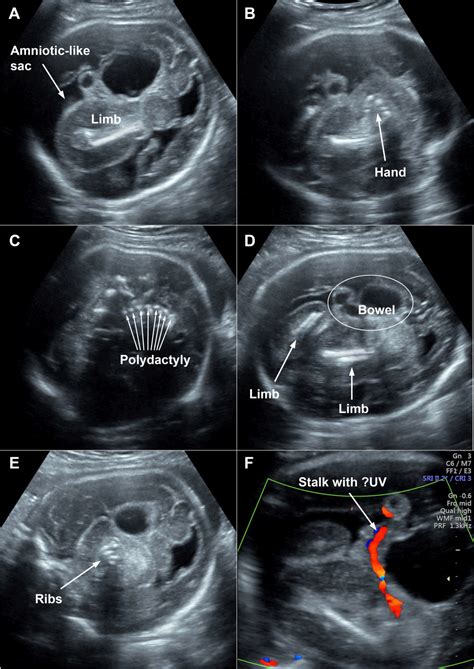

- Intrauteriner Fetus in Fetu: Ein besonders bemerkenswerter Fall aus Kolumbien beschreibt die Diagnose eines Fetus in Fetu bereits in der 35. Schwangerschaftswoche. Eine vermeintliche Leberzyste entpuppte sich als Fruchthöhle mit einem teilweise entwickelten Embryo, der über eine Nabelschnur mit dem Geschwisterkind verbunden war.